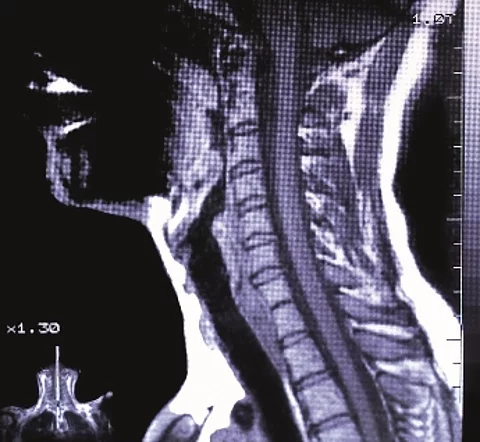

Eine neue Methode ermöglicht es, Gehirntumore können im MRT mit einer Glukoselösung sichtbar zu machen. Diese ist für den Körper deutlich weniger belastend als das üblicherweise verwendete Kontrastmittel.